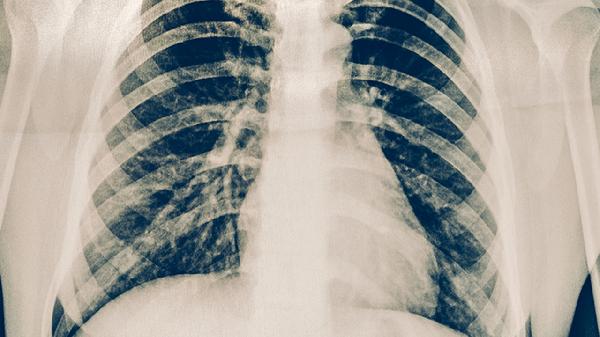

肋软骨炎主要通过体格检查和病史诊断,影像学检查多为排除其他疾病。肋间神经痛可能需要神经电生理检查、胸椎MRI等明确神经受压情况。